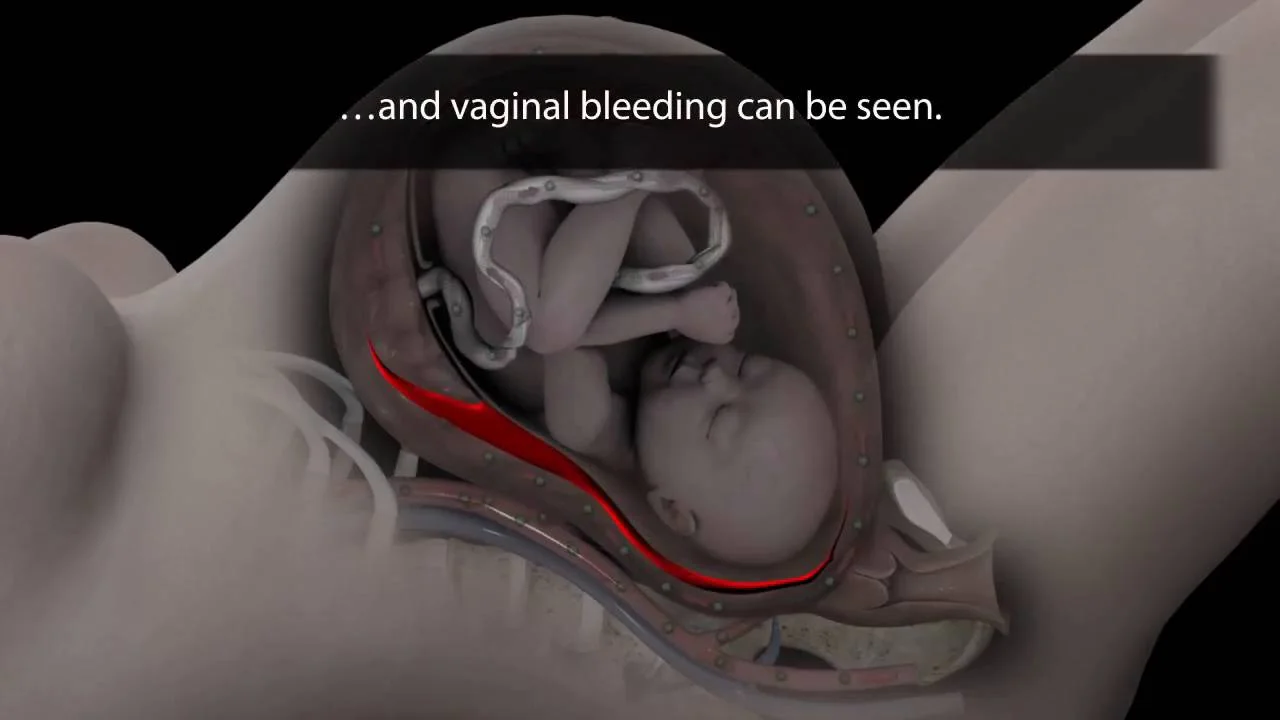

If you’re having an outbreak or symptoms of an impending outbreak when your water breaks or when you go into labor, you’ll need an immediate cesarean delivery. This would be the case if you have any visible sores on your cervix, vagina, or external genitals, or any symptoms, like tingling, burning, or pain, that sometimes signal an imminent outbreak. (Currently, there’s no quick and reliable way to test whether you’re actually shedding virus.)

If you first get genital herpes late in pregnancy and blood tests confirm you’ve never had it before, some experts recommend having a cesarean section even if you don’t have symptoms when you go into labor. About a third of the time, newborn herpes affects a baby’s skin, eyes, or mouth, but not his other organs. If that’s the case, he may have sores at delivery or develop them up to four weeks later. They typically turn up between 1 and 2 weeks of age.